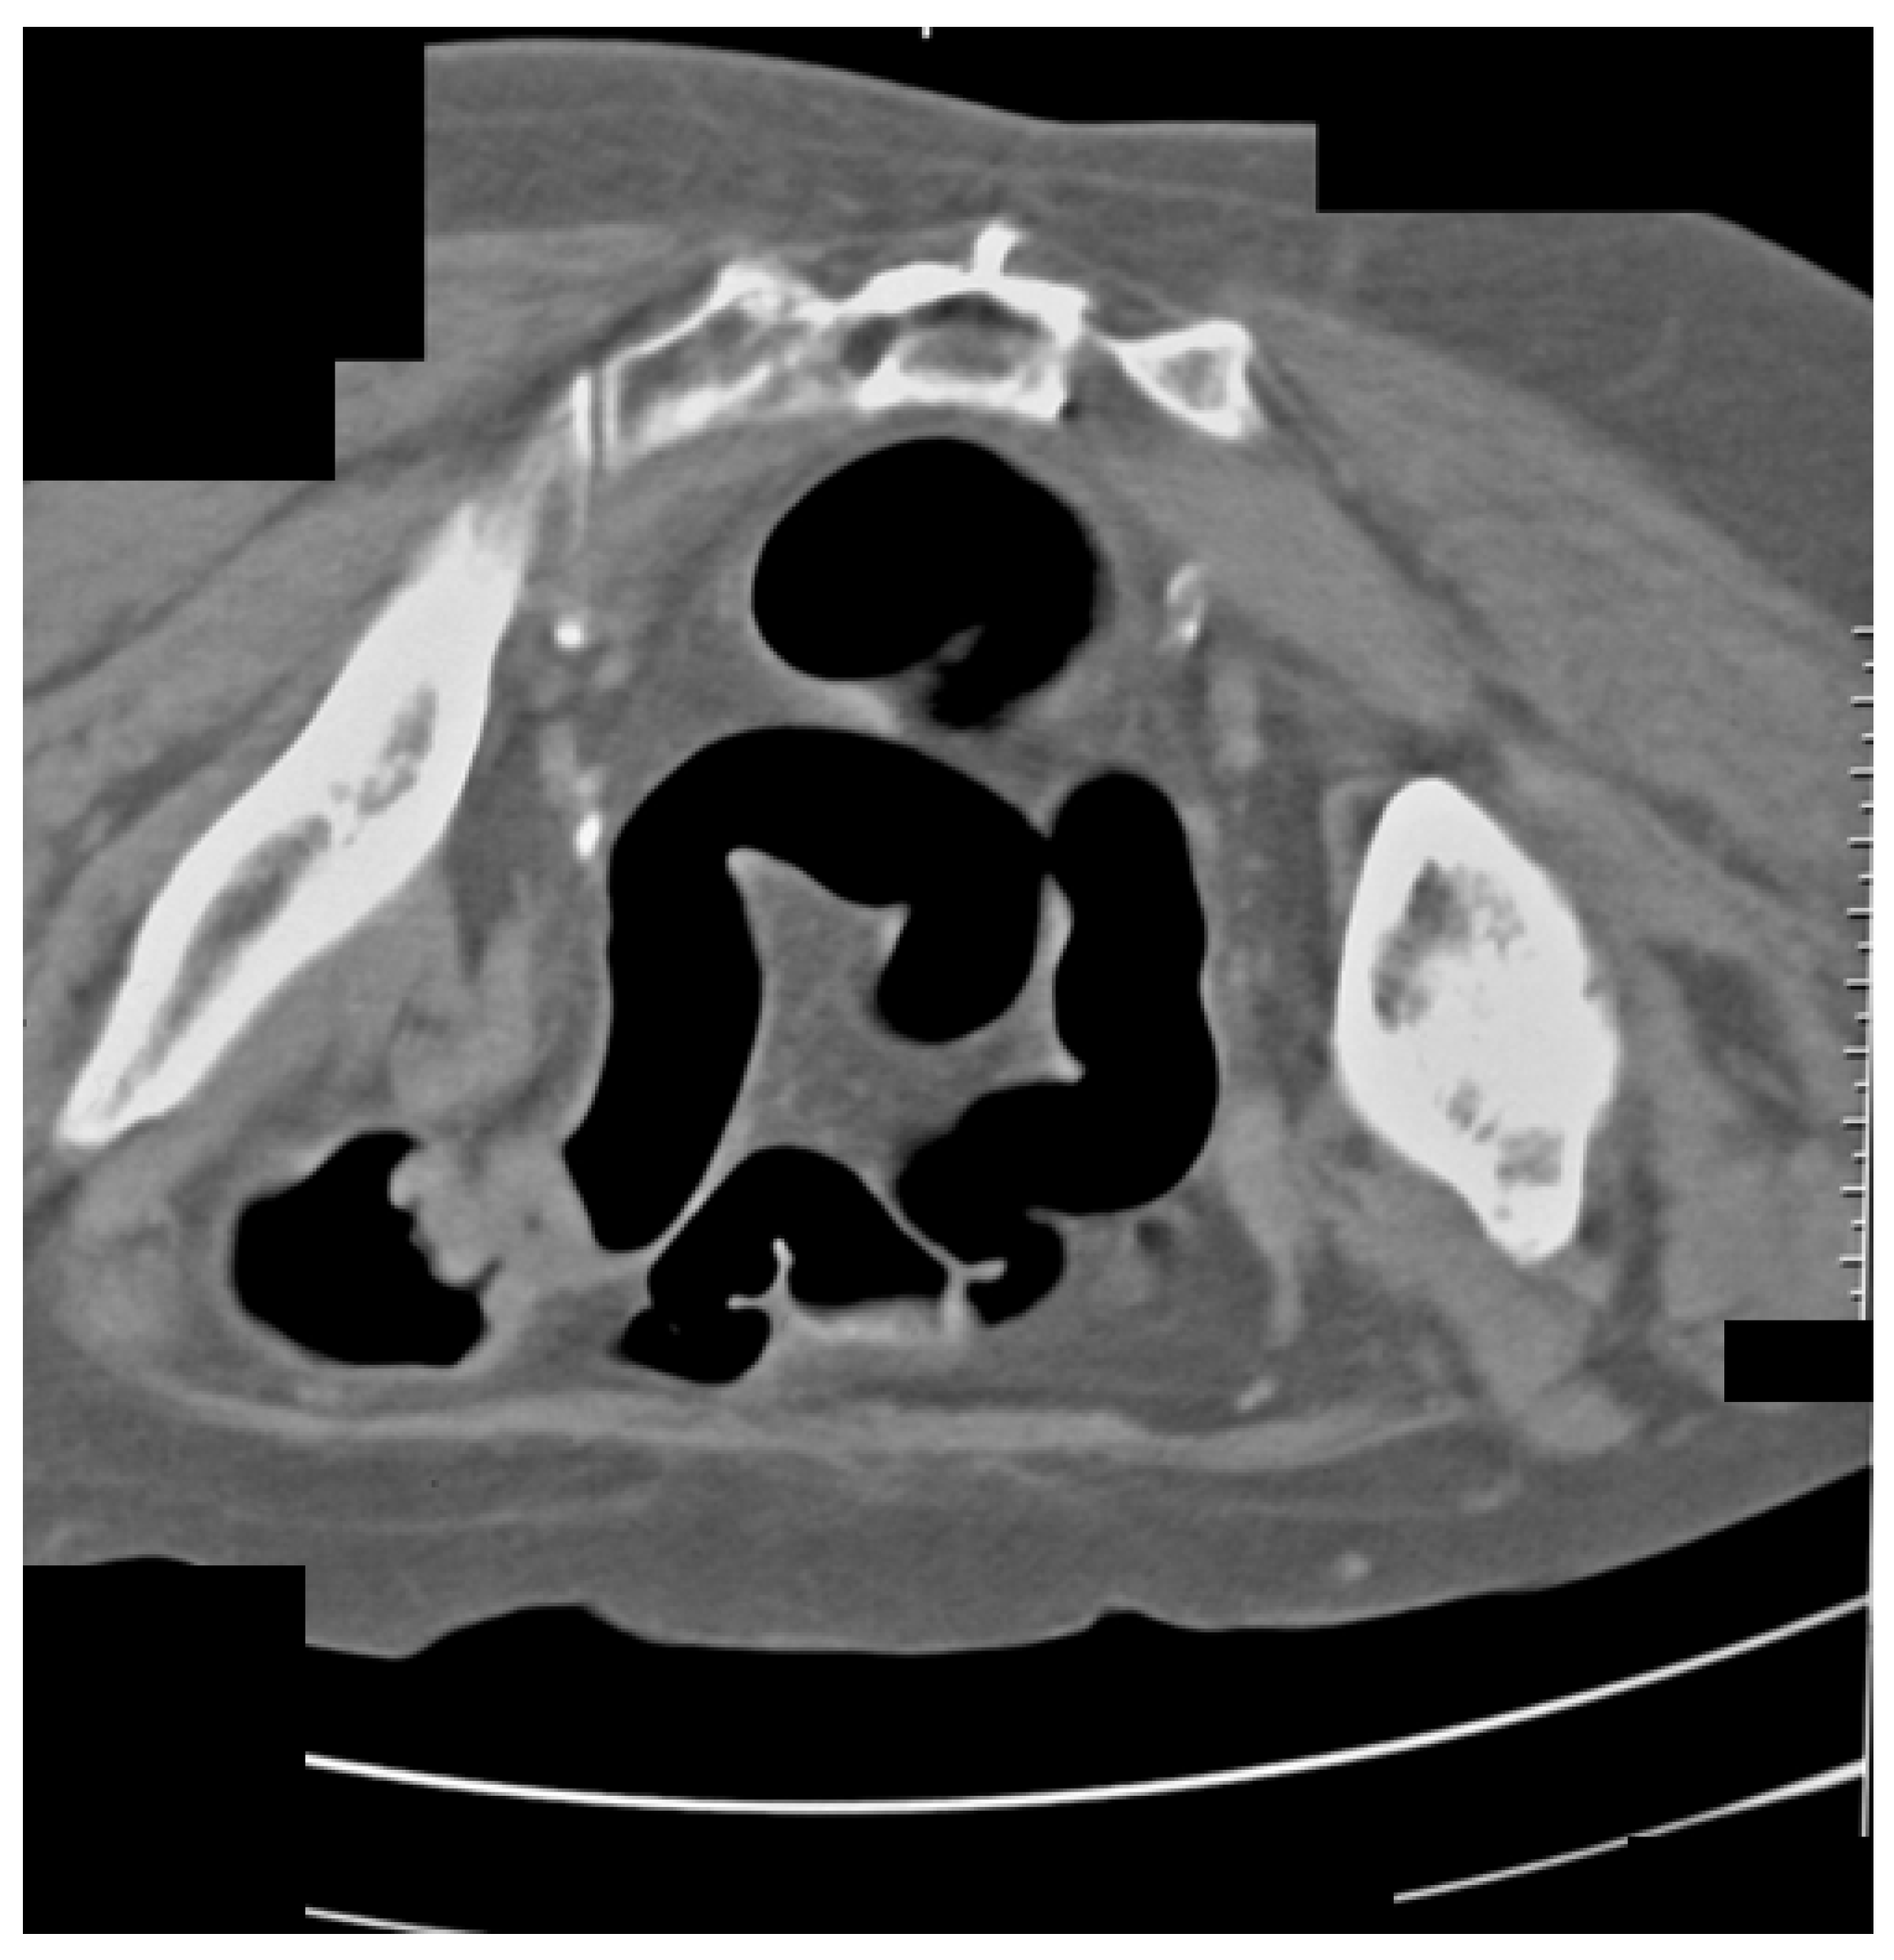

The same patient in the prone position allowed us to visualize carcinoma of the sigmoid colon that rose to the lumen (Figure 4). The differential diagnosis of the finding was residual intestinal contents, which required a change of the patient’s position. Placing the patient in a prone position did not show dynamics in the topic and characteristics of the lesion, which confirmed it was a tumor.

Figure 4.

CT colonography-axial scans in a prone position. The same 73-year-old patient with incomplete FCS due to intraluminal obturation of the sigmoid colon from carcinoma is presented in the figure showing a tumor with soft tissue density.